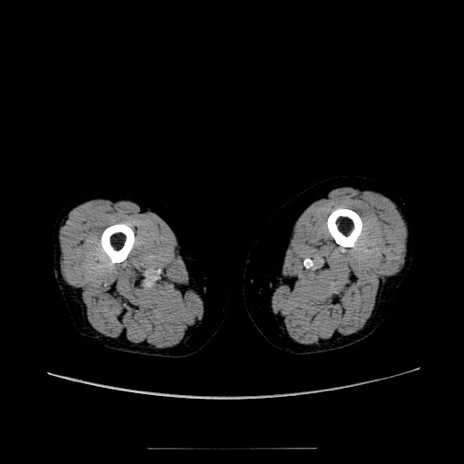

【症例】70歳代女性

【主訴】お腹が張る

【現病歴】1週間くらい前から腹部膨満の自覚あり。昨日夜から増悪したため、本日救急外来受診。

【身体所見】意識清明、BT 36.5℃、BP 165/106mmHg、HR 80bpm、SpO2 98%、腹部:膨満、軟、自発痛・圧痛なし、触診にて不快感あり、腸蠕動音:減弱

【データ】WBC 12600、CRP 1.04